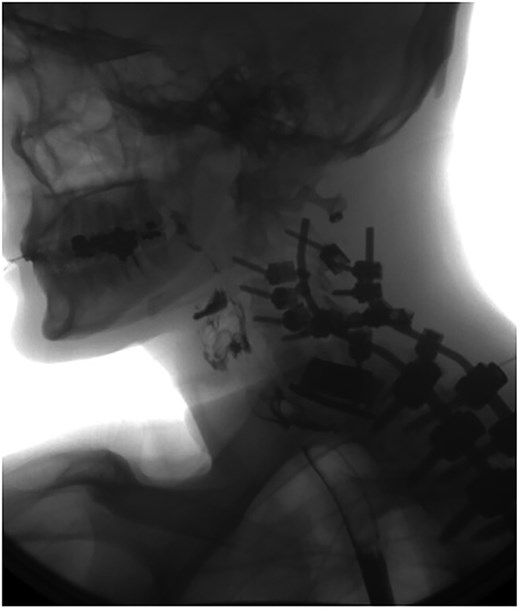

A 35-year-old male presented with a month-long history of dysphagia, severe headache, and posterior neck pain that radiated to the occiput. His medical history was significant for cervical surgeries, including an anterior cervical discectomy and fusion (ACDF) at C5/C6 one year and two months ago (Fig. 1). Shortly thereafter, the patient underwent revision surgery along with posterior plating from C5 to T1 due to osteomyelitis, worsening cervical deformity, and retropharyngeal abscess (Fig. 2). Initial workup included a noncontract computed tomography (CT), demonstrating increased gas density at C6 corpectomy site and post cricoid region (Fig. 3). A swallow study was obtained based on suspicion of a perforation and demonstrated extraluminal leakage of contrast posteriorly at the C6 level, consistent with initial CT (Fig. 4). Surgery included removal of the anterior and posterior hardware and esophageal repair. Although initially the esophageal injury was suspected to be related to the hardware, intraoperatively, it was found the instrumentation was not in communication with the esophagus. This confirmed the perforation was unrelated to direct injury from the cervical hardware construct, which was intact. The esophagus was repaired with a pectoralis flap. The postoperative course was uneventful, and the patient was discharged home after one week. The patient later died due to severe complications of substance abuse unrelated to the operation.

Initial sagittal CT without contrast after patient presented with symptoms of esophageal injury demonstrating increased gas density at the site of C6 corpectomy and post cricoid region.